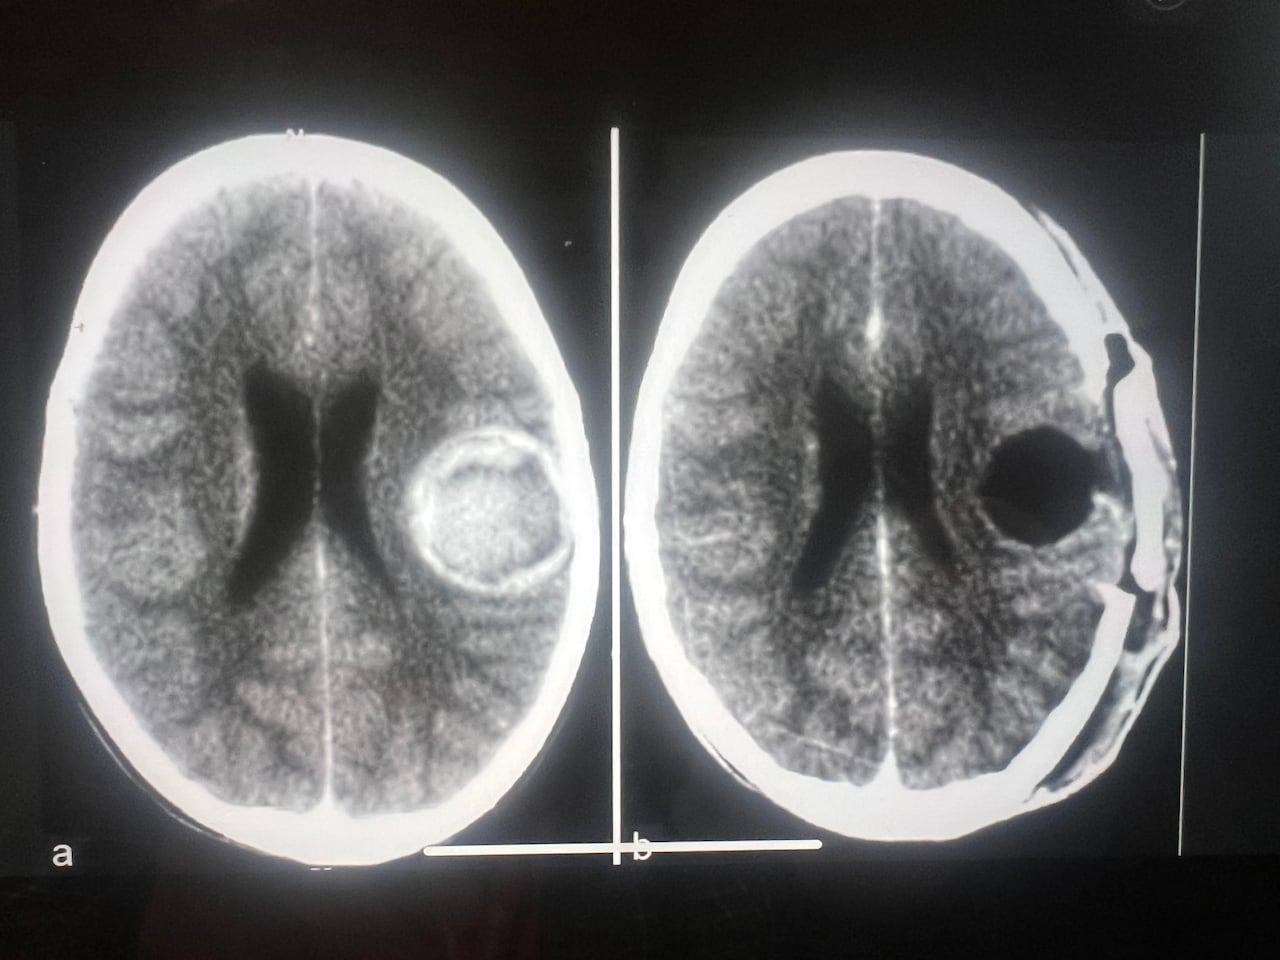

Issues heightened after release from hospitalDuring that hospital visit, a CT scan showed he had a cavernoma in his brain, an abnormal cluster of thin-walled blood vessels. Some people with cavernomas live normal, healthy lives, unaware they even have them. Foster's cavernoma wasn't related to the fall, though it would become significant in the weeks and months after the injury.

He returned to hospital and was told the brain swelling had returned. Doctors decided the cavernoma, about the size of a golf ball, was in the way of his recovery and had to be removed.